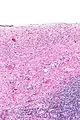

Serous cystadenomas are diagnosed by histomorphologic examination, by pathologists. Grossly, they are, usually, small unilocular cysts that contain clear, straw-coloured fluid. However, they may sometimes be multilocular. Microscopically, the cyst lining consists of a simple epithelium, whose cells may be either:[3]

- be columnar and tall and contain cilia, resembling normal tubal epithelium

- be cuboidal and have no cilia, resembling ovarian surface epithelium

Microscopical images